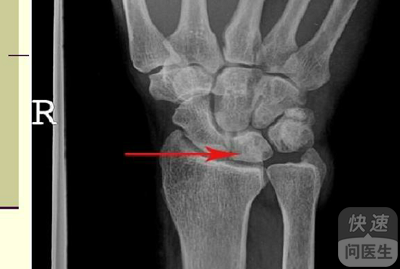

核心提示:关节扭伤,很有可能是行走,奔跑,或者在做什么事情的时候不小心没注意导致关节不小心扭到,造成了一定的损伤,这个时候其实需要进行一定的自行处理。很多人可能并不知道应该怎么处理,那么,接下来小编就来带大家了解一下...